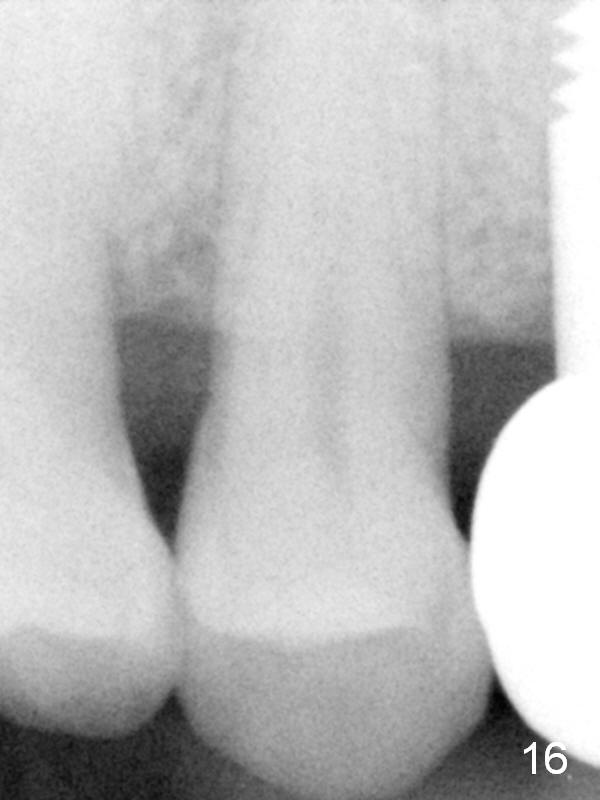

The patient returns 6 months postop for impression of a permanent restoration. The gingiva with knife-edged papillae adapts to the provisional (Fig.7). The gingiva looks healthy when the provisional is removed (Fig.8). The buccal bone resorption seems to be minimal, as compared to Fig.1,2. There is no bone loss between immediately postop (Fig.9 I; implant), 4.5 months postop (Fig.10 A: abutment), 4 and 7 months post cementation (Fig.11,12 C: crown). Soft and hard tissue morphology remains normal 7 months post cementation (Fig.13). No bone loss is observed 15 months post cementation (Fig.14). The papillae (Fig.15) and bone (Fig.16,17) remain stable 29 months post cementation.